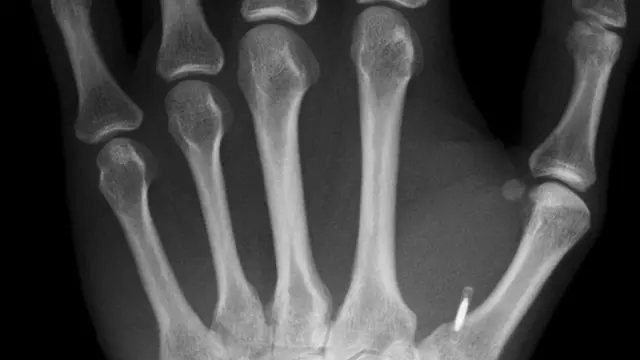

El pequeño abultamiento en la palma de la mano de Dave Williams es apenas perceptible: la mayoría de la gente no notaría a primera vista algo del tamaño de un grano de arroz entre el pulgar y el índice.

Solo cuando el hombre de 33 años abre su puerta con un ademán de la mano es que se hace evidente que algo raro está pasando.

Insertado debajo de la piel de Williams sobresale un implante de microchip, un circuito electrónico dentro de una cápsula de vidrio en forma de píldora, el cual se puede utilizar como una tarjeta de crédito sin necesidad de contacto.

Las preocupaciones de vigilancia sobre el chip colocado en la parte posterior de su mano no inquietan a Dave Williams, ya que solo se puede activar si se coloca a pocos centímetros de un lector.

También está interesado en enfatizar que el procedimiento para implantarlo no es tan doloroso o complejo como algunos podrían imaginar.

Williams se instaló su chip él mismo, usando mucho yodo para mantener todo estéril.

"Casi no hubo dolor", dice. "Retirar el dispositivo sería un poco más difícil pero con un bisturí y un par de pinzas no es tan terrible".